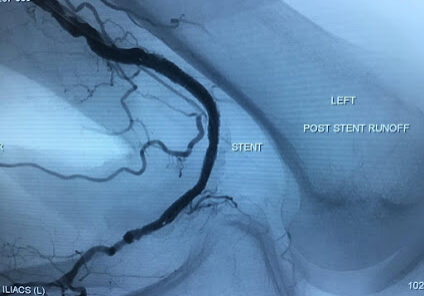

Gore Viabahn VBX Covered Stent plays important role in addressing complex aorta-iliac occlusive3

Gore Viabahn VBX Covered Stent plays important role in addressing complex aorta-iliac occlusive.

Is Gore VBX a better alternative for CERAB reconstructions2

Is Gore VBX a better alternative for CERAB reconstructions?

VBX as primary choice

VBX as primary choice for complex aorto-iliac reconstructions.